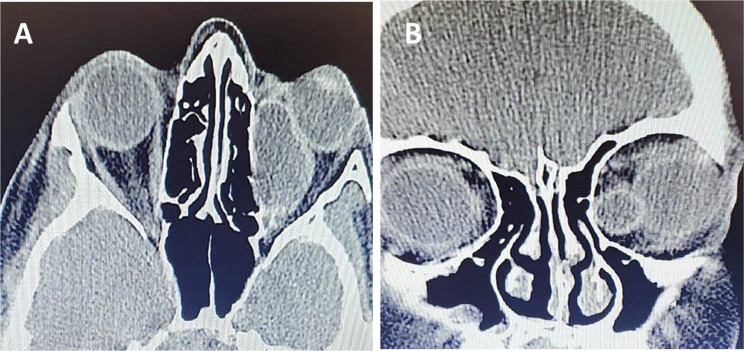

Case presentation: A 12-year-old boy presented with a one-month history of diplopia and left-sided proptosis. A CT scan revealed a cystic mass within the left medial rectus muscle. Surgical intervention confirmed the presence of a hydatid cyst following cyst rupture and irrigation with hypertonic saline. The patient underwent a two-month course of albendazole therapy. Initially, the patient experienced persistent exotropia and diplopia, but at the three-year follow-up, he exhibited no diplopia or proptosis and only mild residual exotropia.